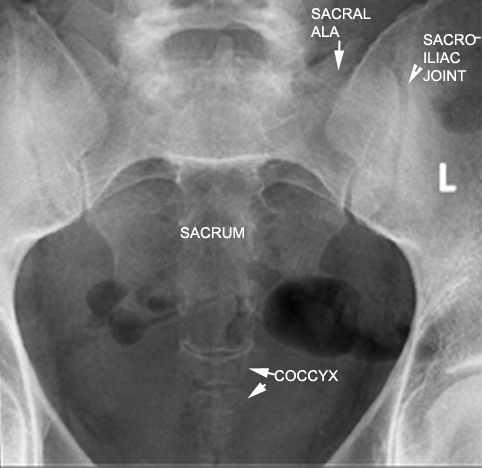

Identify parts of the sacrum and coccyx. Click the image for labeling.